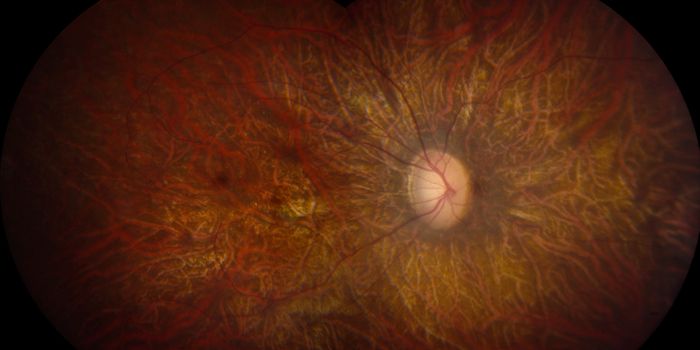

JUN 24, 2022Plants & AnimalsWe’ve all what animals see. Do they see the same way humans do in terms of colors, or is the vision of each animal ...